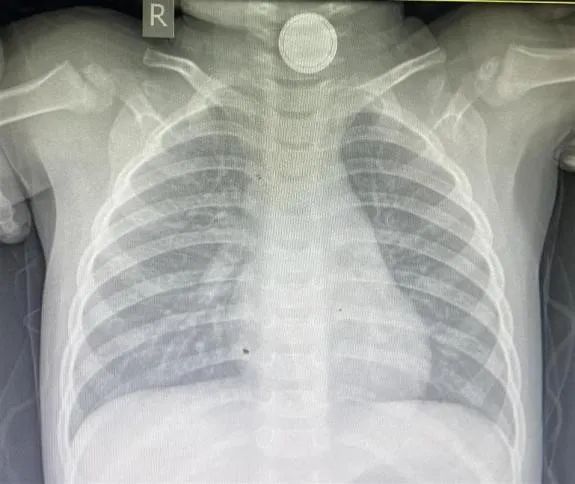

新闻媒体上也不时会报道误吞纽扣电池出现受伤的案例,如2024年4月,湖北一名1岁男童误吞了一枚纽扣电池,卡在了食道,造成吞咽困难,医生经手术从其体内取出一块烧焦的电池,电池的渗出液严重腐蚀了孩子的食道,留下一块指甲盖大小的黑痂。(图2)

图2 检查影像和取出的纽扣电池(图源网络)为了预防儿童误吞纽扣电池带来的风险,消费者需要采取以下措施: